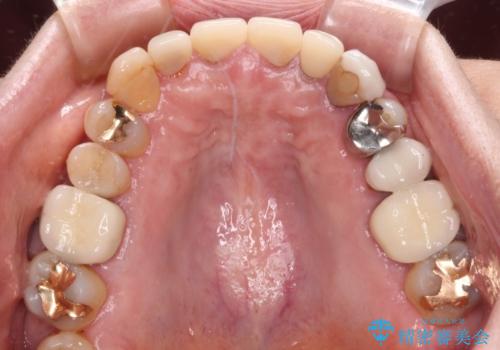

- 前歯が土台ごと外れてしまったとのことで来院された患者様です。

土台は外れていましたが破折などの問題はなく、土台からの再治療で対応可能な状態でした。

隣の犬歯も神経が取り除かれていたしたが、ラミネートベニアで治療されており、裏側でむし歯が進行する可能性があったため、こちらも治療が必要と判断されました。

今回の治療を機会に前歯全体をやり直すことも考えたそうですが、取り急ぎ要治療となった2歯を先に治療することとしました。